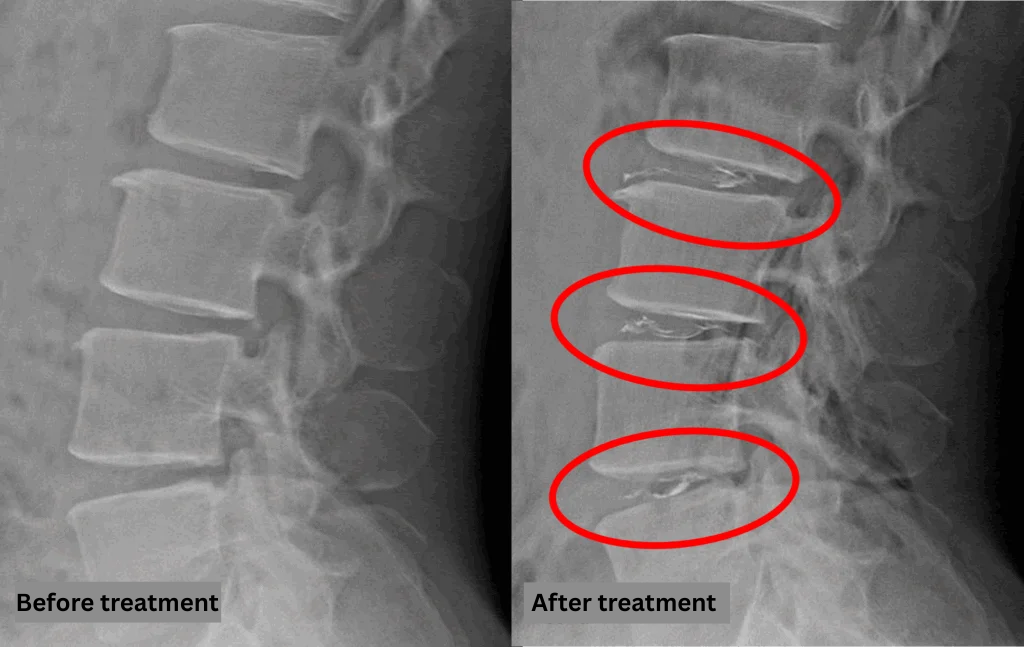

- L2/3, L3/4, L4/5: Disc degeneration and bulging

The above findings were also observed on the imaging.

These findings suggest that disc degeneration and associated bulging at L2/3, L3/4, and L4/5 may be the primary contributors to the patient’s symptoms.

After consulting with the patient, the Cellgel Method was performed on L2/3, 3/4 and 4/5.